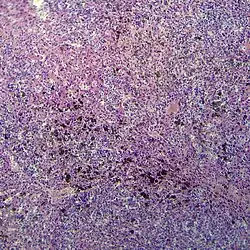

- Окончательный диагноз меланомы может быть установлен только после гистологического исследования, проведённого после тотального удаления невуса (опухоли) с достаточным захватом здоровых тканей. Предоперационная биопсия с помощью иглы или частичного удаления противопоказана, во избежание распространения меланомы. Определяется глубина прорастания (Clark, Breslow) и митотический индекс.